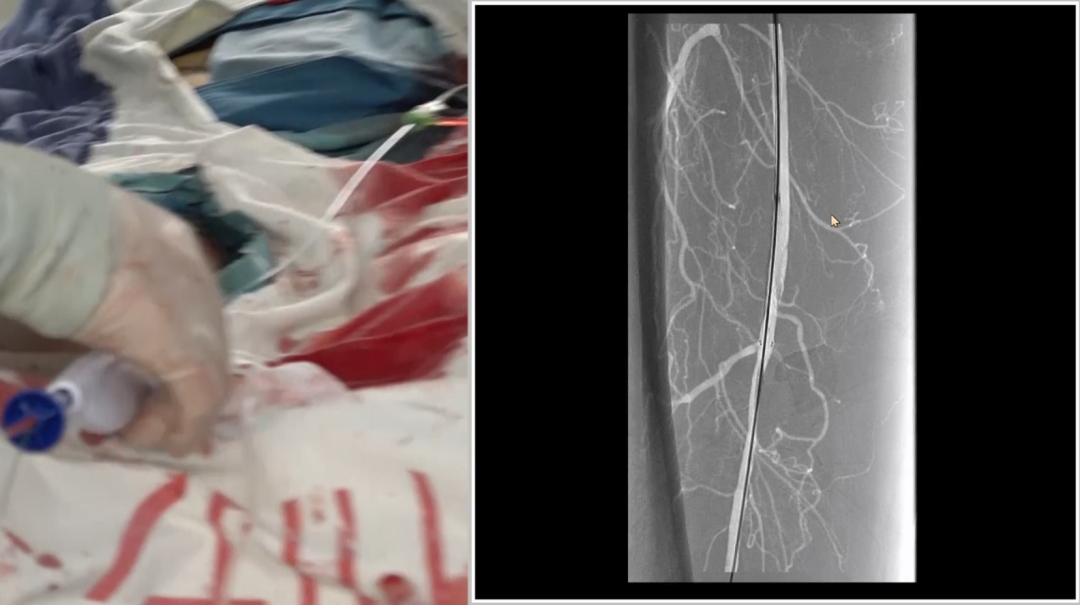

导丝突破:多种器械配合,应对坚硬病变

初始使用单弯导管配合Command18导丝尝试突破股动脉起始段纤维帽,未成功;

更换Terumo导丝后突破纤维帽,但支撑导管跟进困难,提示病变质地坚硬;

先后尝试Command 18、Treasure12 CTO导丝等,均难以顺利通过病变段;

关键技巧:采用"自制CTO导丝"——剪除V18导丝部分软头,塑形后利用其强支撑性,顺利通过病变并跟进支撑导管。

远端困境:

内膜下难以返回真腔,果断选择逆穿

导丝进入远端内膜下后,反复尝试返回真腔失败。为避免过度操作损伤远端流出道,团队决定行逆向穿刺(逆穿):

调整球管至左前斜20°~30°,在路图下定位穿刺点;

近端推注造影剂,透视下确认血管位置,穿刺成功(可见明显充盈缺损);

跟进V18导丝突破远端纤维帽,配合支撑导管完成对接。

逆穿的难点在于选择合适的对接位置,对接判断要点是导丝成袢后,通过近端Terumo导丝触碰,若有明显"碰触感",提示位于同一内膜下,可确认对接。